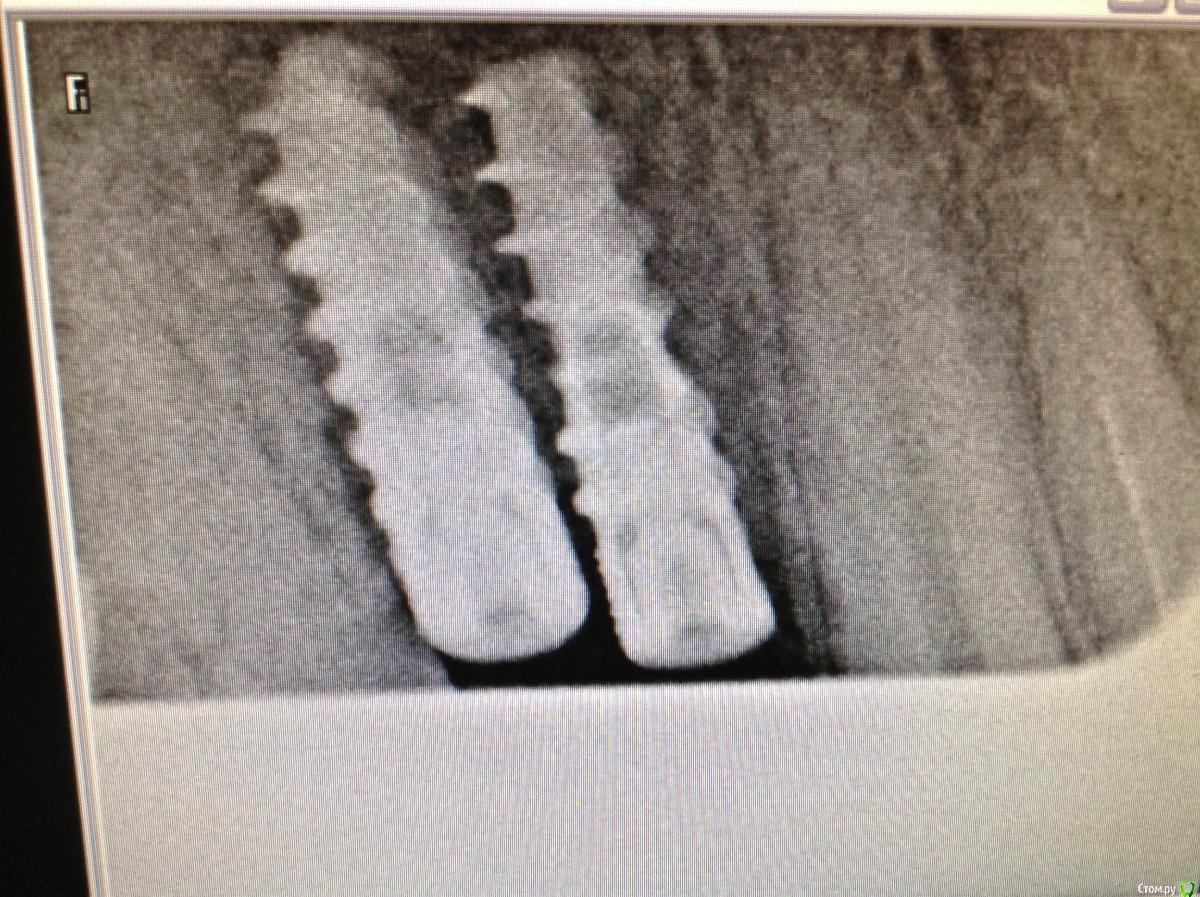

ksenistom Опубликовано 2 декабря, 2014 Поделиться Опубликовано 2 декабря, 2014 Уважаемые коллеги,подскажите пожалуйста,как быть в данной клинической ситуации? Ссылка на комментарий

ksenistom Опубликовано 2 декабря, 2014 Автор Поделиться Опубликовано 2 декабря, 2014 Почему места недостаточно?)) Все получится, даже у среднеграмотного техника. Где одиночка, премолярчик выйдет)Мне хирург так и сказал,только что мне с 6 делать?там все вплотную,расстояние должно 1,5мм минимум быть? Ссылка на комментарий

chernov Опубликовано 2 декабря, 2014 Поделиться Опубликовано 2 декабря, 2014 Мне хирург так и сказал,только что мне с 6 делать?там все вплотную,расстояние должно 1,5мм минимум быть?от чего-до чего,расстояние должно быть?знаете? Ссылка на комментарий

ksenistom Опубликовано 2 декабря, 2014 Автор Поделиться Опубликовано 2 декабря, 2014 от чего-до чего,расстояние должно быть?знаете?От зуба до импланта 1,5мм,между имплантатами 3мм или я ошибаюсь? Ссылка на комментарий

chernov Опубликовано 2 декабря, 2014 Поделиться Опубликовано 2 декабря, 2014 От зуба до импланта 1,5мм,между имплантатами 3мм или я ошибаюсь?1,5мм ширина костной перегородки для формирования сосочка,а конструктивно(для техника) разницы нет. Ссылка на комментарий

Dman Опубликовано 2 декабря, 2014 Поделиться Опубликовано 2 декабря, 2014 с планированием беда какая-то вышла) 1 Ссылка на комментарий

Heatshock Опубликовано 4 декабря, 2014 Поделиться Опубликовано 4 декабря, 2014 хирургический шаблон явно не в почете у хирурга) Ссылка на комментарий